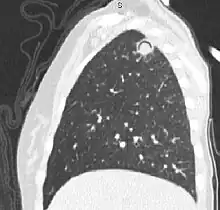

| The arrows denote an ill-defined nodular opacity in medial aspect of right upper lobe with ill-defined rim of lucency surrounding it | |

In radiology, the air crescent sign is a finding on chest radiograph and computed tomography that is crescenteric and radiolucent, due to a lung cavity that is filled with air and has a round radiopaque mass.[1] Classically, it is due to an aspergilloma, a form of aspergillosis, that occurs when the fungus Aspergillus grows in a cavity in the lung.[2] It is also referred as Monad sign.[3]

Sagittal reformat from a CT scan of the chest showing air crescent sign in a patient with invasive fungal infection. There is a rounded cavity in the apical right upper lobe, with a non-dependant soft-tissue nodule within it. Also there is some subtle ground-glass opacity surrounding the lesion.